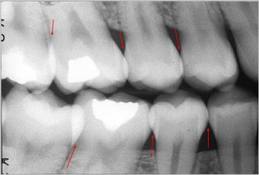

Si las radiografías están disponibles, el

primer paso es clasificar las lesiones de caries coronal en

dientes posteriores de acuerdo con los grados que están en

la Tabla 4.

Sistema radiográfico ICDAS

(Radiografía Bite-Wing) |

Sano |

R0 |

No hay

radiolucidez |

Estadios

iniciales * |

|

RA1 |

Radiolucidez en

1/2 externa del esmalte |

RA2 |

Radiolucidez

en la 1/2 interna del esmalte ± UAD

(Unión amelo-dentinaria) |

Se lo considera aún un estadio

inicial porque no hay dentina

infectada ) |

RA3 |

limitada al 1/3 externo de la

dentina |

Estadio

moderado

(En este estadió

comiemza la infección de la dentina por bacterias orales) |

RB4 |

Radiolucidez que

alcanza hasta el 1/3 medio de la

severos

(Infección franca de la dentina) |

RC5 |

alcanza hasta el 1/3 interno de la

dentina, clínicamente cavitada

RC6 |

la pulpa, clínicamente cavitada

*

Nota- La

mayoría de lesiones confinadas al esmalte no

se ven en las radiografías.

Tabla 4: Clasificación

radiográfica ICDAS